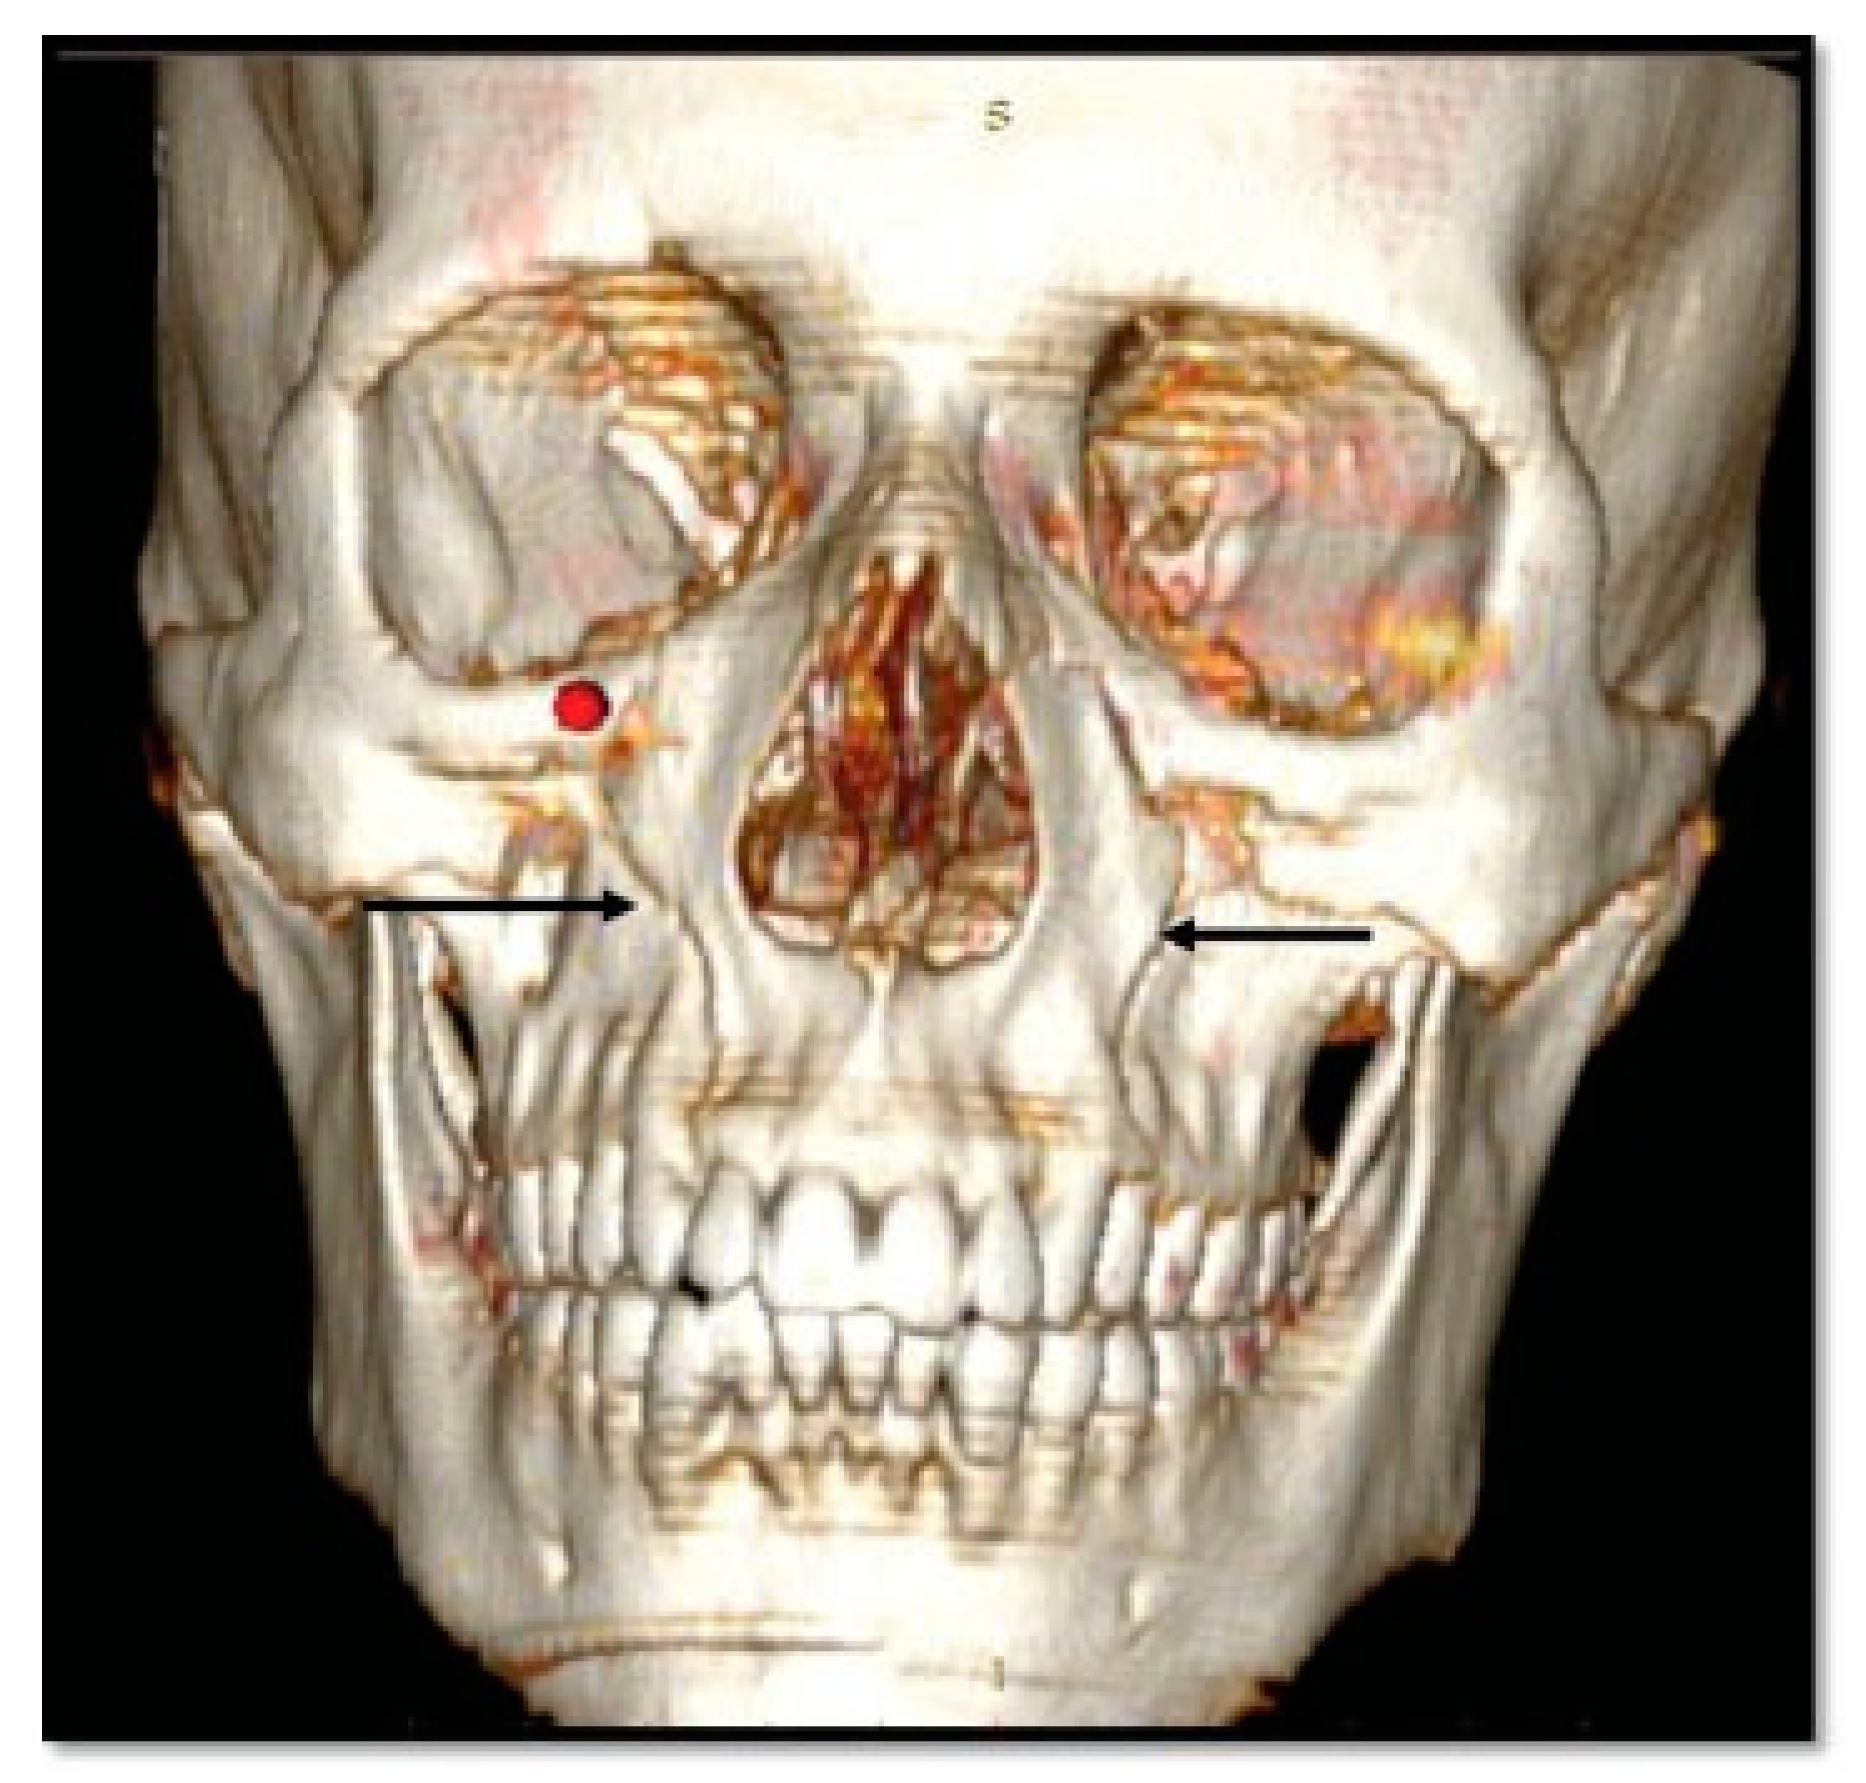

- Additional line extending from the pyriform aperture to the infraorbital rim of the same side (60%).

- Additional line extending from the infraorbital rim to the Le Fort fracture line.

- Additional line extending from the pyriform aperture to the lateral wall of orbit, without breaking the infraorbital rim of the same side (5.4%).

- Additional line extending from the infraorbital rim through the canine fossa to terminate as a fractured dentoalveolar segment of the same side, involving the fractured segment (10.9%).

- Pterygoid plates are not fractured (23.6%).

- D1: Additional Line Extending from the Pyriform Aperture to the Infraorbital Rim of the Same Side (34.5%)

- D2: Additional Line Extending from Infraorbital Rim to the Le Fort Fracture Line (25.4%)

- D3: Additional Line Extending from Pyriform Fossa to Lateral Wall of Orbit, without the Fracture of the Infraorbital Rim of the Same Side (5.4%)

- D4: Additional Line Running from the Infraorbital Rim through the Canine Fossa to Terminate as a Fractured Dentoalveolar Segment of the Same Side (10.9%)

- D5: Pterygoid Plates Are Not Fractured (23.6%)